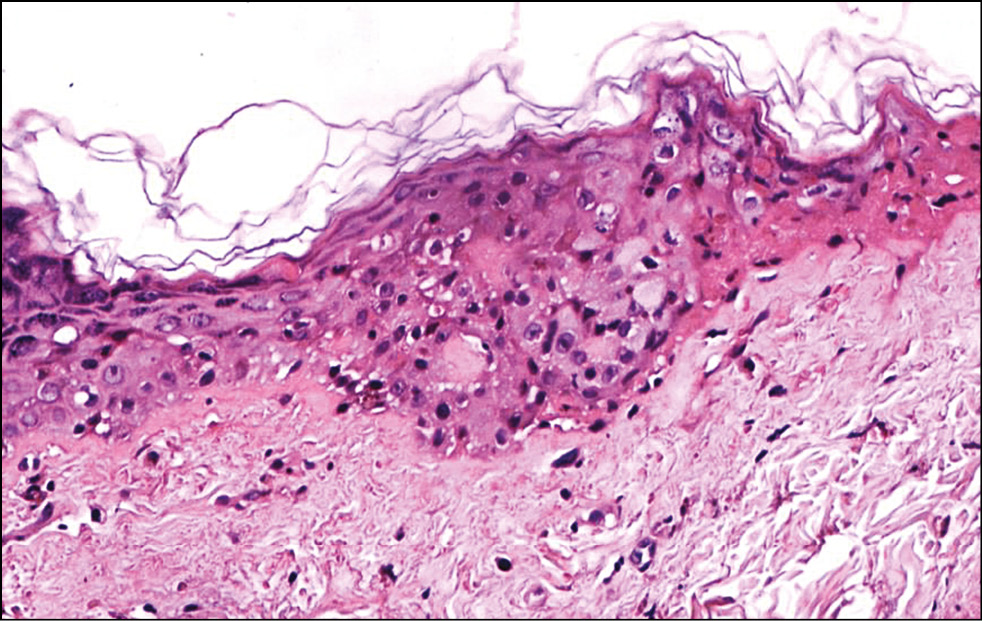

Рис. 6. Гистологическая картина кожи заушной области женщин через 30 мин после фотодинамической терапии. Окраска гематоксилином и эозином, x200.

Fig. 6. Histological picture of the skin behind the ear of women 30 minutes after photodynamic therapy. Hematoxylin and eosin staining, x200.

Подэтап 2А. Гистологическое исследование показало, что сразу после воздействия ФДТ (рис. 6) в коже обнаруживались единичные лейкоциты в толще эпидермиса и на его поверхности; ядра клеток эпидермиса и их цитоплазма на данном участке были набухшие, сосочки дермы несколько сглажены, рыхлая волокнистая соединительная ткань сосочкового слоя дермы отёчна. На третий день (рис. 7) после процедуры отмечено уменьшение количества набухших ядер в эпидермисе, заметны мелкоочаговые кровоизлияния в сетчатом слое дермы с перифокальной сосудистой реакцией и слабовыраженным отёком сетчатого слоя дермы. Спустя 20 дней (рис. 8) после воздействия заметна умеренная пролиферация клеток эпидермиса и дермы. Отмечается уплотнение коллагеновых волокон сетчатой дермы. Патологических изменений в эпидермисе, дерме, придатках кожи не обнаружено.

Таким образом, воздействие на кожу человека длиной волны 660 нм в течение 30 мин с использованием фотосенсибилизатора Сферометаллохлорина™ является безопасным и не приводит к развитию патологических реакций.